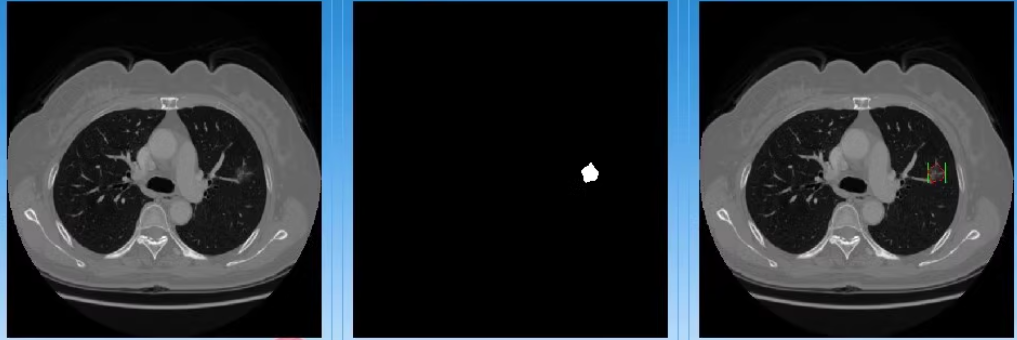

通过python语言 pyqt5界面 建立 基于深度学习的CT医学图像分割检测系统

构建一个CT图像分割检测系统,有那个 登录界面、图像加载、分割和检测功能,使用Python和PyQt5。

4. 实现分割和检测逻辑

通过以上步骤,同学你可以构建一个完整的CT图像分割检测系统,包括登录界面、图像加载、分割和检测功能。